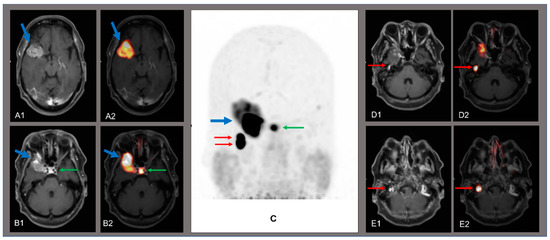

Treglia, G.; Raditchkova, M.; Giovanella, L.; Stelmes, J.-J.; Bosetti, D.G.; Martucci, F. Two Birds with One Stone: Skull Base Meningioma and Jugulotympanic Paragangliomas with Somatostatin Receptor Positron Emission Tomography. Diagnostics 2021, 11, 1669. https://doi.org/10.3390/diagnostics11091669